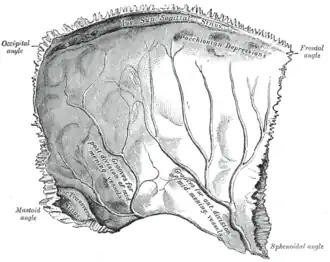

-

Left parietal bone. Inner surface. -